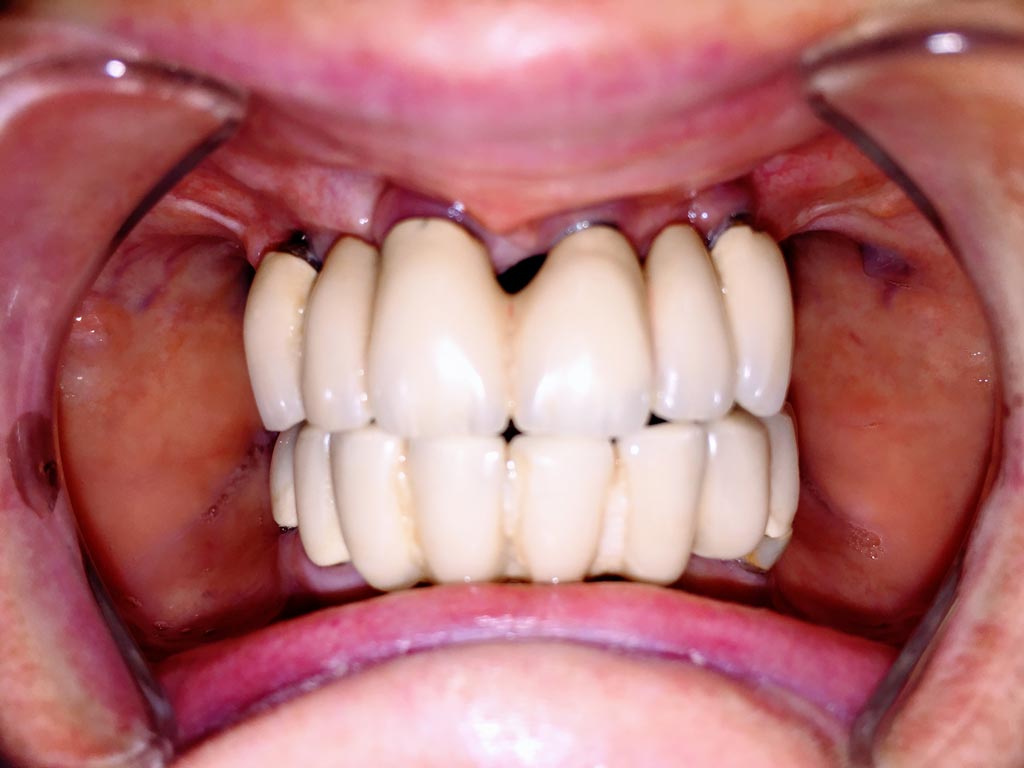

Elhanyagolt fogsor cseréje 2 nap alatt

2 nap alatt varázsoltuk ezt a szép esztétikus alsó, felső körhídat implantátumokkal megtámasztva a korábban elhanyagolt szájba. Az 1. nap 26 fogat távolítottunk el, mert annyira rossz állapotban voltak, és rögtön azonnal terhelhető IHDE svájci implantátumokat raktunk be, fentre 8, lentre 6 darabot. A sebeket összevarrtuk és intraorális szkennerrel digitális lenyomatot vettünk. 2 nap múlva pedig beragasztottuk a kész PMMA műanyag körhidakat. Dr. Kelemen Péter és a Symbion Fogtechnika munkája.